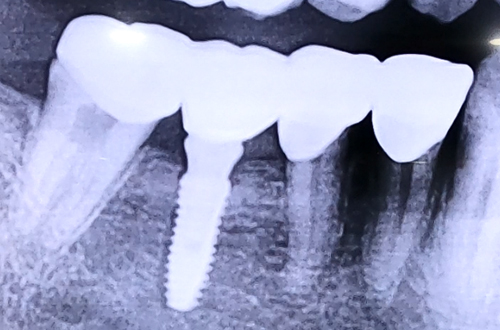

브릿지 제거 후 임플란트 치료 사례

BEFORE

아주 오래전에 브릿지 치료를 받았던 어금니의 잇몸이 자꾸 붓고 염증이 생기고 씹을 때마다 통증이 있는 등의 증상으로 내원해주신 환자분입니다.

오른쪽 아래 뒤에서 두번째 큰 어금니를 예전에 발치한 뒤 브릿지 치료를 받으신 상태로, 브릿지 보철이 가진 단점 탓에 통증, 부기, 염증 등 잇몸 증상들이 나타나고 있는 상태셨는데요.

브릿지가 가진 특징 때문에 생기는 증상이므로, 브릿지를 제거한 뒤 치아 한 개씩 정상적인 힘만 받도록 개별적으로 치아를 씌워드리고 이가 없는 자리에는 임플란트를 식립하여 치료해 드렸습니다.